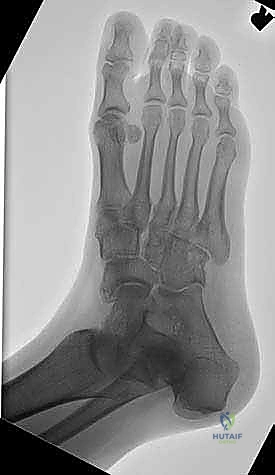

- الأشعة السينية أثناء الوقوف (Weight-bearing X-rays): وهي أهم أداة تشخيصية. الأشعة العادية والسرير فارغ لا تظهر المشكلة الحقيقية؛ يجب التقاط الأشعة والمريض يقف ليتحمل وزن الجسم، مما يظهر الانهيار الفعلي للمفاصل وتضيق المسافات بين العظام.

- الأشعة المقطعية (CT Scan): توفر صوراً ثلاثية الأبعاد للعظام، وهي ضرورية جداً للتخطيط الجراحي الدقيق وتحديد مدى التلف العظمي والزوايا المطلوبة للتثبيت.